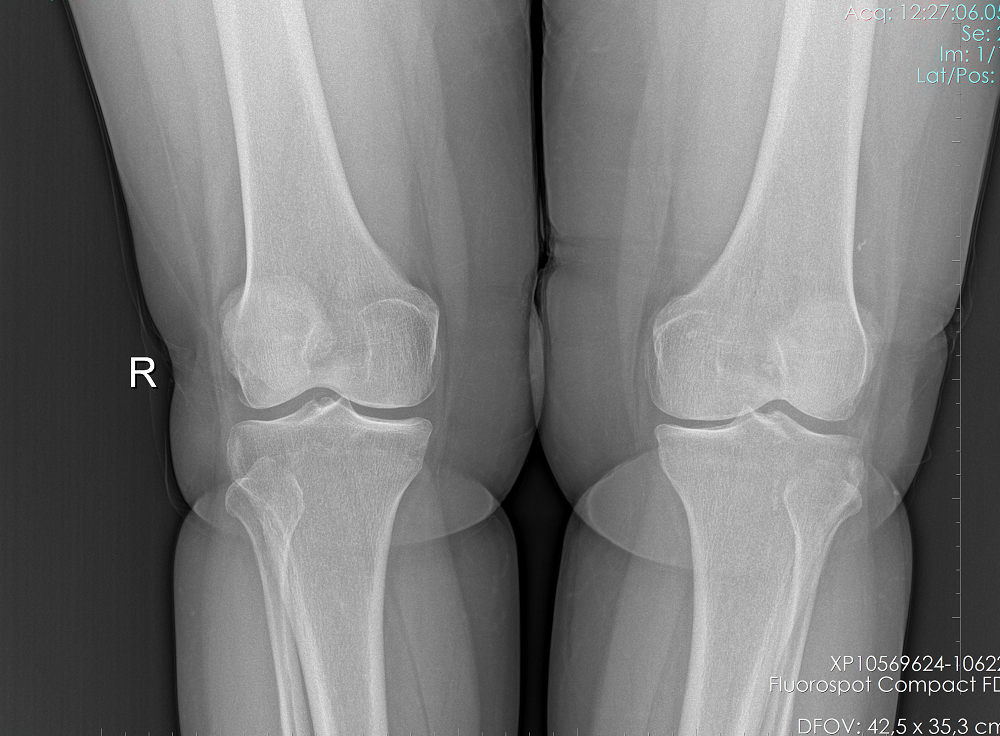

Gonartrozu olan hastanın ameliyat öncesi ve YTO yapıldıktan sonraki grafileri